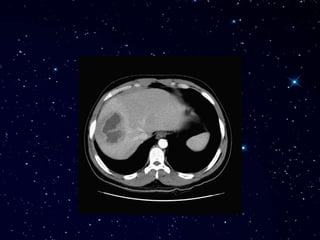

Зураг